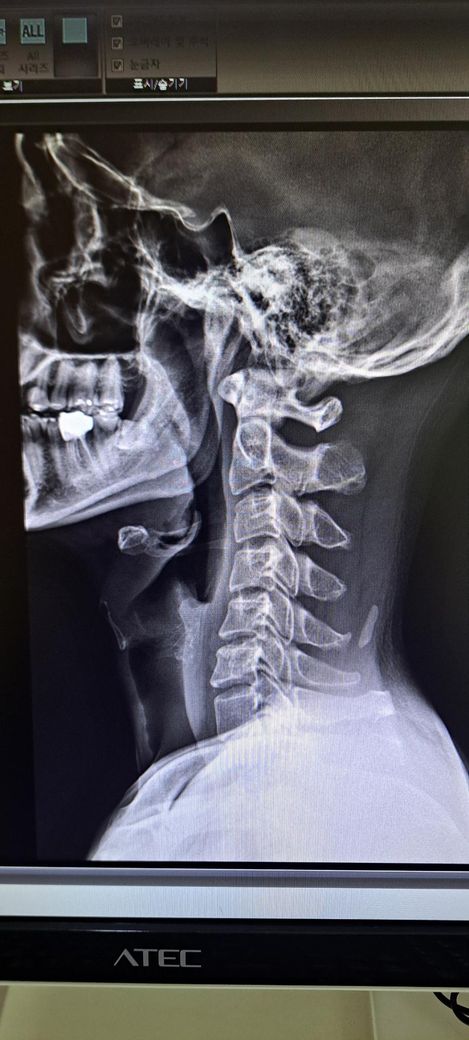

또한 일자목도 있다는데 심각한 정도인가요?

목은 일자목 경향은 있으나 심한 변형보다는 자세성 문제로 보이며 교정운동이 중요합니다.

또한 목은 일자목이 있으며 역C자 수준 까지는 아니라고 생각됩니다.

정면 사진상 골반의 좌우높이 차이가 관찰되며, 이는 대퇴골의 위치변화와 연관되어 보입니다. 측면 사진에서 요추의 곡선이 다소 꺾여 있는 양상이 보여 골반 전방경사 가능성이 큽니다. 정면 영상에서 척추가 일직선이 아니라 완만한 S자 형태로 휘어있는 측만 소견이 보입니다. 심각한 수준은 아니나 지속적인 관리가 필요한 상태입니다. 측면 사진상 경추의 커브를 보면 일자목 상태입니다. 골반이 높은쪽의 근육은 이완시키고, 낮은쪽과 약해진 둔근, 복근을 강화하는 운동이 필요합니다. 전방경사 완화를 위해 장요근 스트레칭과 프랭크 같은 코어 운동이 효과적입니다. 흉쇄유돌근 스트레칭과 더불어 등 근육을 강화하여 어깨를 펴는것이 급선무입니다.

보여주신 X-ray를 보면 우선 첫번째 사진에서 경추전만이 무너져서 일자목을 넘어 역 C자가 만들어진걸 볼 수 있습니다. 평소 고개를 앞으로 굽히지 않는 경추전만 자세 교정이 필요하겠으며 아래 영상 보시면서 자세를 교정해보시기 바랍니다. 아래 영상은 디스크에 대한 영상이지만 결국 교정해야할 자세는 같습니다.

x-ray 결과로 보아서는 경추C자 곡선이 반대로 되어 있어 일자목이 심해 보이며 골반 틀어짐과 척추측만증이 있는 것으로 보입니다.

신체 전반적으로 불균형과 척추 변형이 있기 때문에 경추부터 요추, 골반까지 전체적인 교정이 필요해 보입니다.